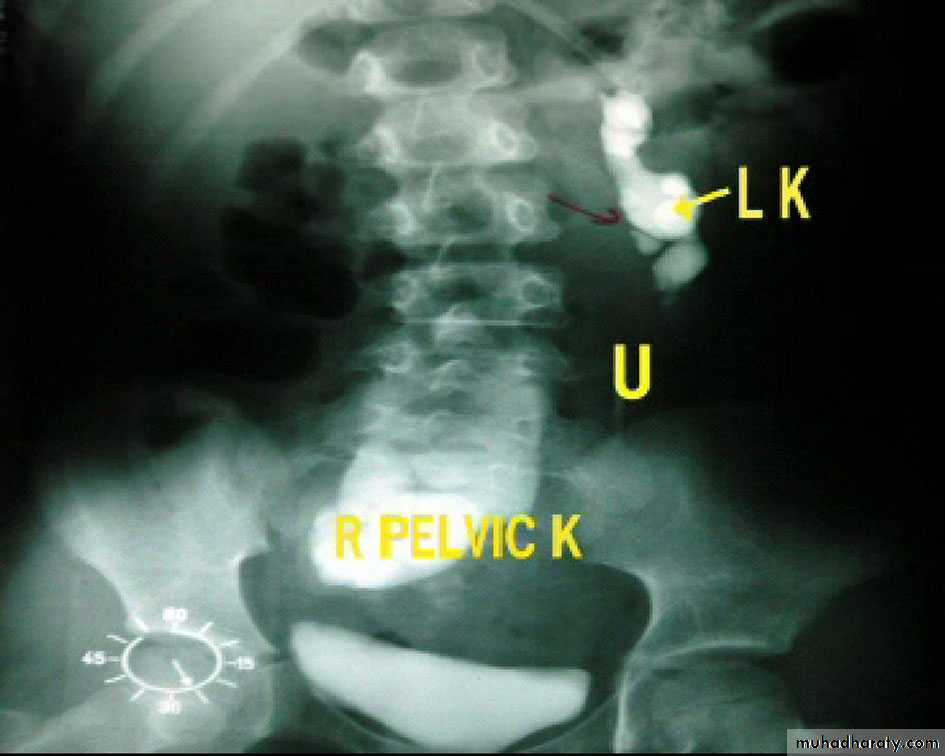

Ectopic kidney:

- Result from halted ascend of kidneys during fetal development

- Often are incidental findings during routine ultrasound, -usually located in the lower abdomen and rotated, -short ureter.

-Chronic pyelonephritis, calculi and hydronephrosis are more common .

Horse shoe kidney -Kidneys may fail to separate.

-Almost invariably the lower poles remain fused.

-The kidneys axes are more parallel to the spine and malrotated.

-Diagnosis can be made by plain x-ray in some cases.

-US, CT scan and MRI can better demonstrate the anatomy and morphology hence the diagnosis.

-May be an incidental finding.

-PUJ obstruction and calculi formation are common .

IVU shows

1. The kidneys at low position .

2.Close to the spine with long axis parallel to the spine .

3. Malrotation manifested by medially directed calyces.

4- The renal pelvis and ureters are anterior and lateral in position .